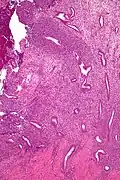

Low mag. -